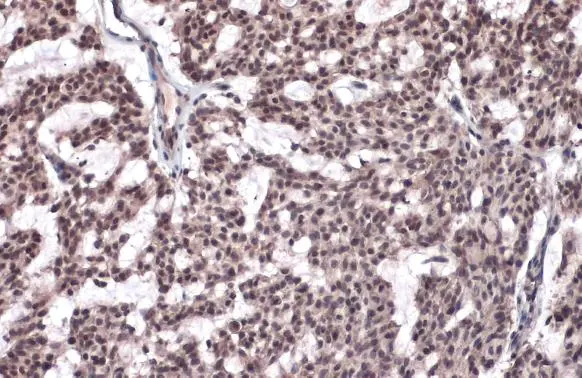

Anti-Histone H2A.XS139ph (phospho Ser139) antibody used in IHC (Paraffin sections) (IHC-P). GTX127340

GTX127340 IHC-P Image

Histone H2A.XS139ph (phospho Ser139) antibody detects Histone H2A.XS139ph (phospho Ser139) protein at nucleus by immunohistochemical analysis.

Sample: Paraffin-embedded human breast carcinoma.

Histone H2A.XS139ph (phospho Ser139) stained by Histone H2A.XS139ph (phospho Ser139) antibody (GTX127340) diluted at 1:500.

Antigen Retrieval: Citrate buffer, pH 6.0, 15 min